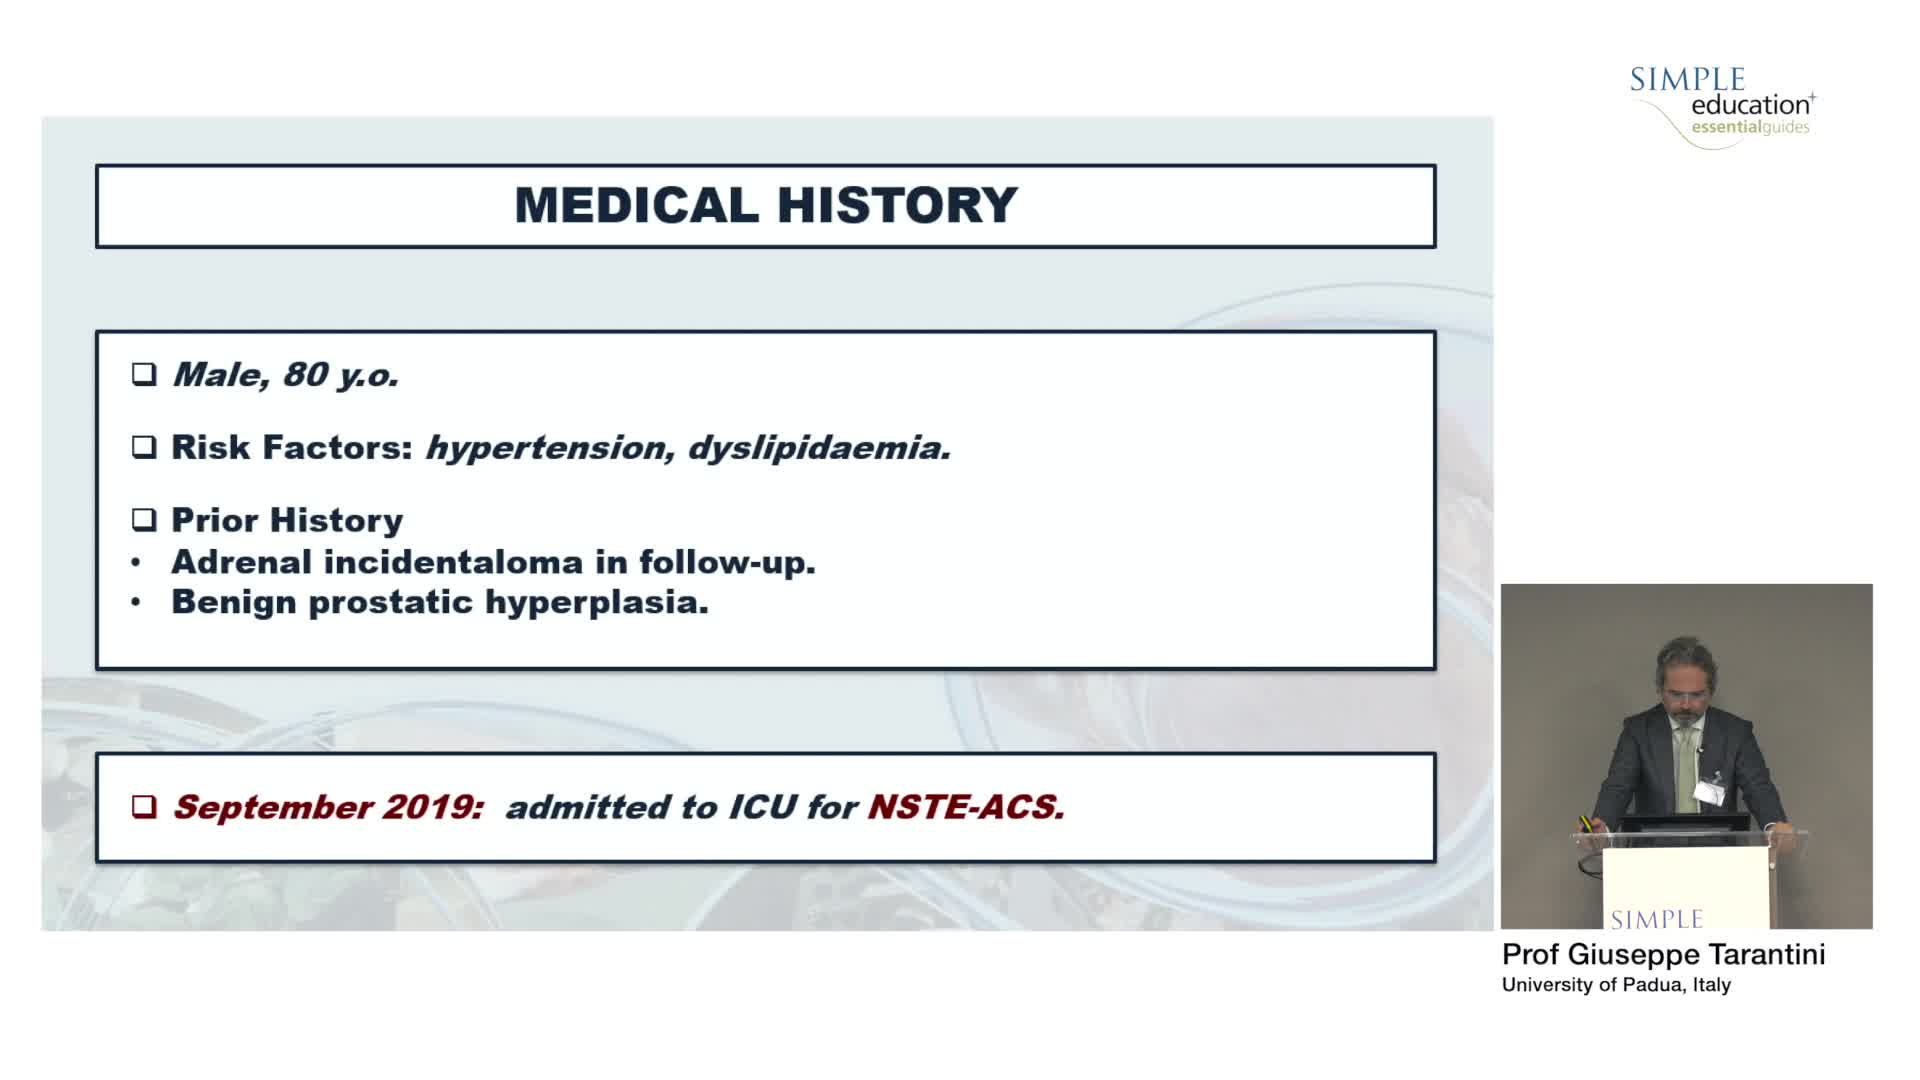

Using SyncVision Co-registration to distinguish between focal and diffuse coronary disease. - Prof Giuseppe Tarantini

Intracoronary guidance in acute coronary syndromes - Dr Hernan Mejia-Renteria